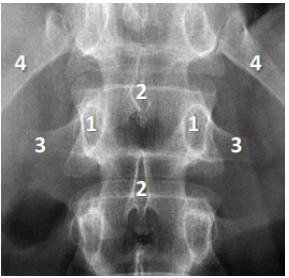

7

Q

A

1. Pedículo

2. Processo espinhoso

3. Processo transverso

4. Última costela (12a)